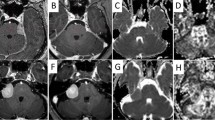

Image Postprocessing and Data Measurement

All image acquisitions were processed using Diffusional Kurtosis Estimator (DKE) [23] and analyzed using MATLAB tools created in-house. All measures (including FA, MD, λa, λr, MK, Ka, and Kr) were reconstructed following the standard configuration for DKE [23]. Maps of diffusion and perfusion parameters are shown in Figs. 2 and 3. We first identified the slice as close to the spectral location T2-WI anatomy as possible. One uniform circular regions of interest (ROI) was placed in each temporal lobe white matter in the b = 0 images in two consecutive sections. A radiologist who was blinded to the patients’ identities manually place the ROIs. A code was written to make sure that the diameter for the circular region was 6 mm. The size of the ROIs was about 28 mm2. Measures were acquired and averaged within each individual ROI. Each lesion was measured twice in two separate sessions spaced 2 weeks apart to ensure reproducibility and showed satisfactory intraobserver agreement with an error of 4.0% coefficient of variance only.

Axial views of diffusion kurtosis imaging (DKI)-derived parametric maps for a 40-year-old woman with nasopharyngeal carcinoma during radiotherapy. a Fractional anisotropy (FA); b mean diffusivity (MD); c axial kurtosis (Ka); d radial kurtosis (Kr); e axial diffusivity (λa); f radial diffusivity (λr); g mean kurtosis (MK)

Axial views of diffusion kurtosis imaging (DKI)-derived parametric maps for a 40-year-old woman with nasopharyngeal carcinoma at 1 month after radiotherapy. a Fractional anisotropy (FA); b mean diffusivity (MD); c axial kurtosis (Ka); d radial kurtosis (Kr); e axial diffusivity (λa); f radial diffusivity (λr); g mean kurtosis (MK)